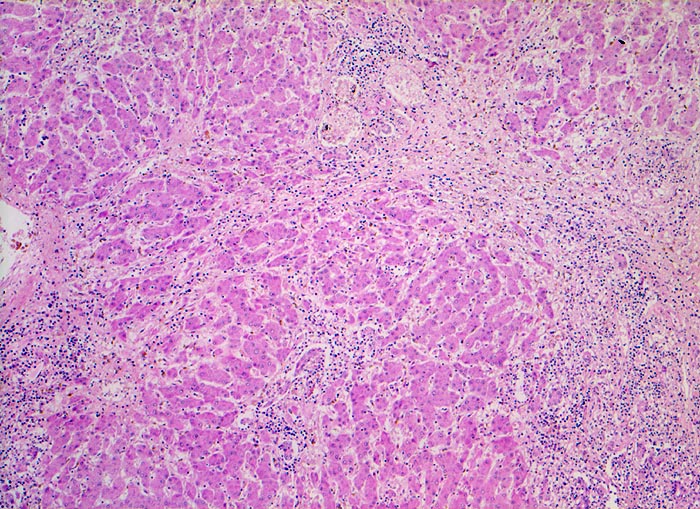

PathoPic ID 5136 - akute Hepatitis

akute Hepatitis

Entzündung infektiös

Leber

Vergösserte Portalfelder mit dichten lymphohistiozytären und granulozytären Infiltraten.

Autopsiepräparat eines 37jährigen Patienten mit Transaminasenanstieg und Hyperbilirubinämie

Histologie

50